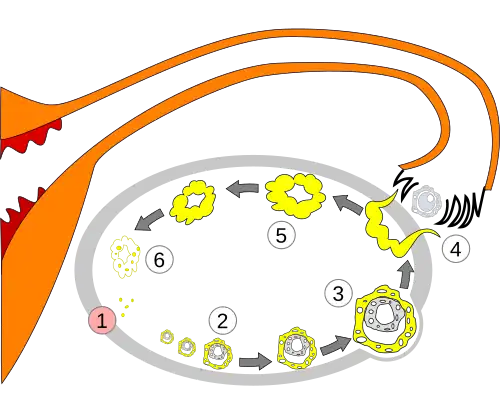

-

Order of changes in ovary -